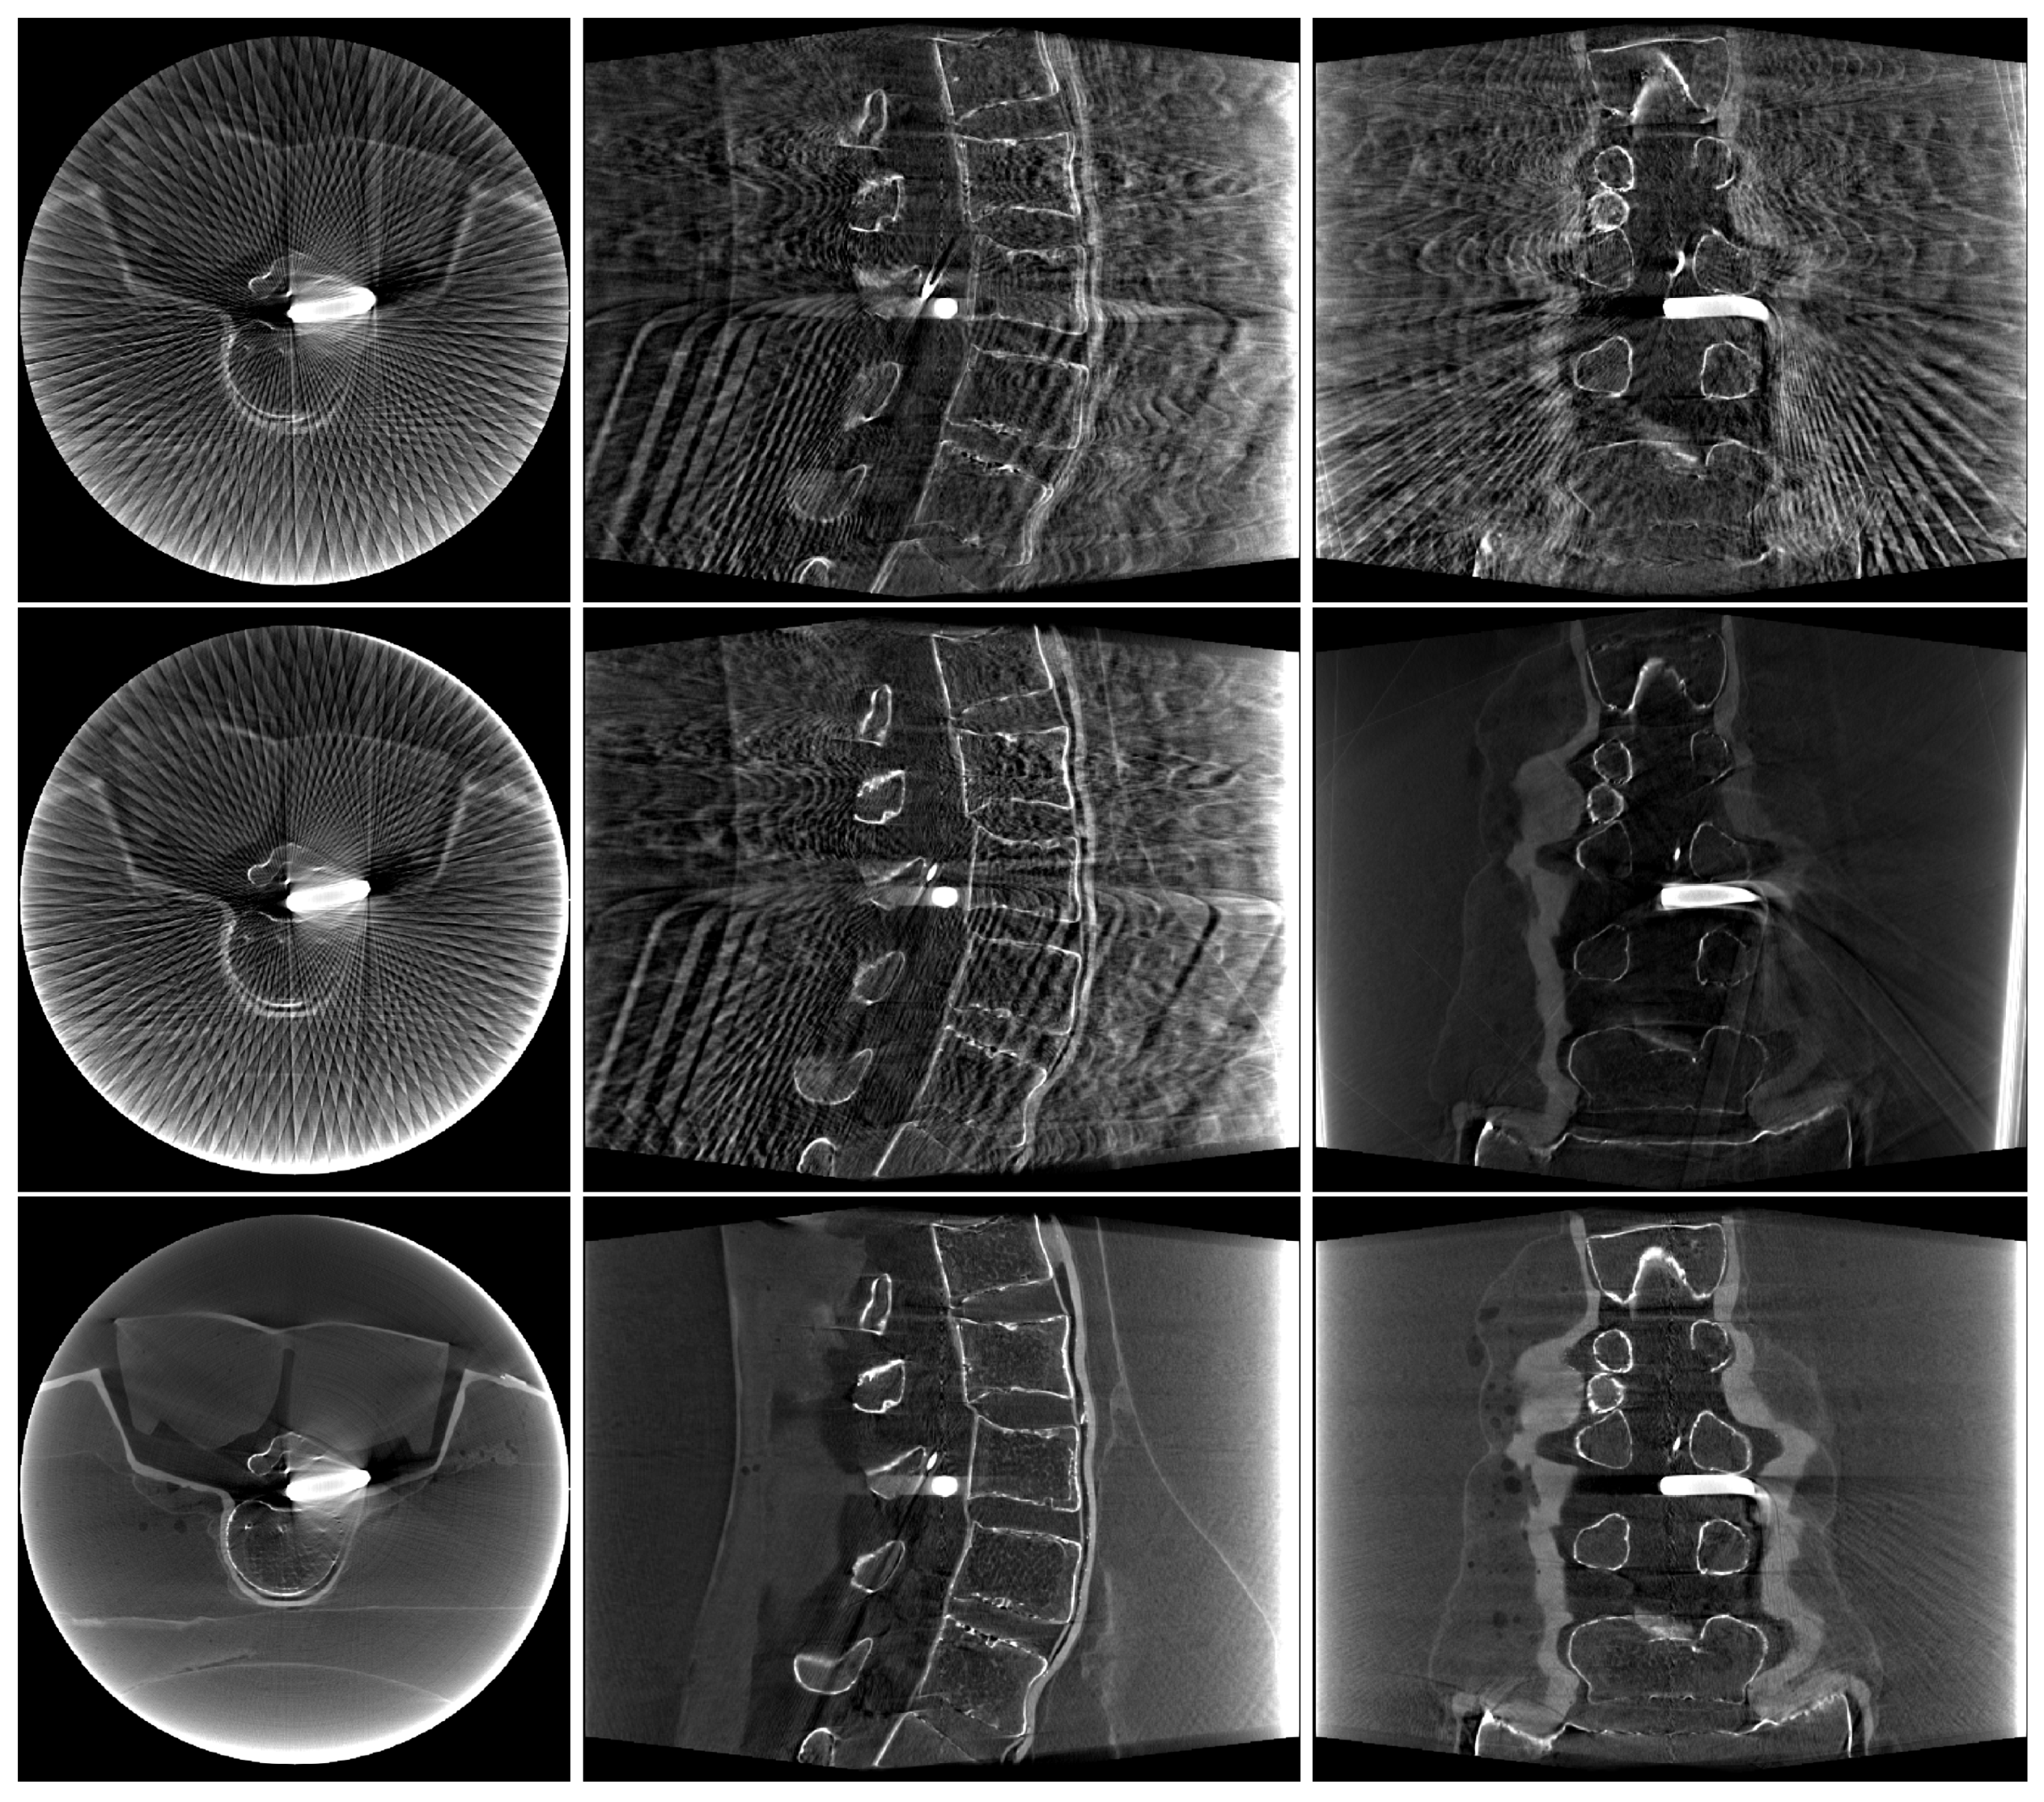

2. Materials and Methods

3. Results